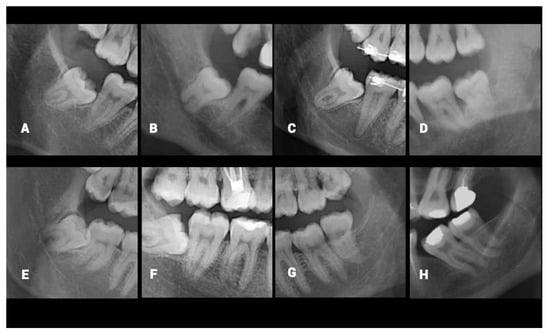

The dentomaxillofacial radiologists conducting the present study evaluated the misclassified cases and noted some particular radiological limitations caused by superimposition or uncertainty in the ROI. The main characteristics of those limitations were the ill-defined superior border of MC, narrowing of the MC, dilacerated root morphology of M3, the ghost image of the opposite inferior border of the mandible, superimposition of the lateral border of the tongue, failed segmentation, bifid MC variation, and superimposition of the mylohyoid ridge. The characteristics were depicted in Figure 3. The same limitations were asked of dental practitioners and they all stated that the cases in which the superior cortical border of MC is not clear, were the hardest to classify. Despite the M3s having untraceable relation with the MCs being excluded from the dataset by the specialists, it is clear that the high number of radiographic variations is a factor that makes it difficult to determine the MC-M3 relationship.

Figure 3. Examples of the misclassified mandibular canal and mandibular third molar overlap by the algorithm and the possible characteristics that cause misclassification: (A), Ill-defined superior border of MC; (B), Narrowing of the MC; (C), Dilacerated root morphology of M3; (D), The ghost image of the opposite inferior border of mandible; (E), Superimposition of the lateral border of the tongue; (F), Failed segmentation; (G), Bifid MC; (H), Superimposition of the mylohyoid ridge.